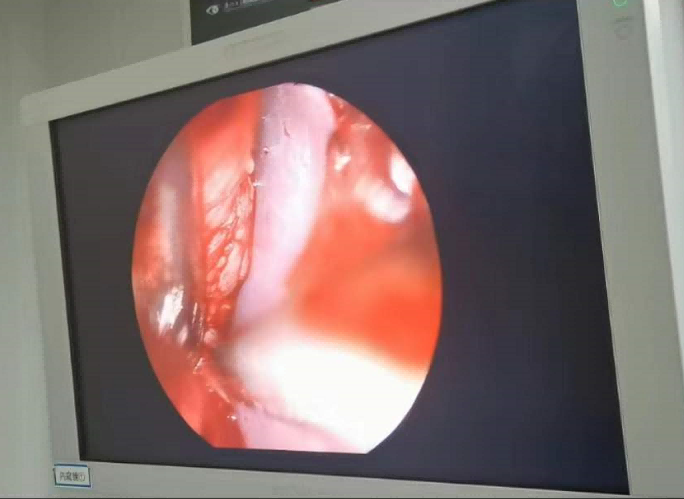

送到廈門眼科中心的時(shí)候,林老師受傷的左眼還在流血。眼整形科的鄧?yán)っ鞲敝魅吾t(yī)師緊急為他安排了“內(nèi)鏡下眶骨折修補(bǔ)+鈦網(wǎng)鈦釘植入術(shù)”。

圖為:內(nèi)鏡下眼眶骨折修補(bǔ)術(shù)

手術(shù)過(guò)程中林老師還出現(xiàn)了驚險(xiǎn)的眼球后大出血,還好鄧?yán)っ饔诰o急之中穩(wěn)住了病情,并順利完成了手術(shù)。術(shù)后第二天,林老師的術(shù)后反應(yīng)就很輕,恢復(fù)良好,他一邊感謝著鄧?yán)っ鞯?ldquo;救命之恩”,一邊自嘲著自己示范了個(gè)“反面教材”。